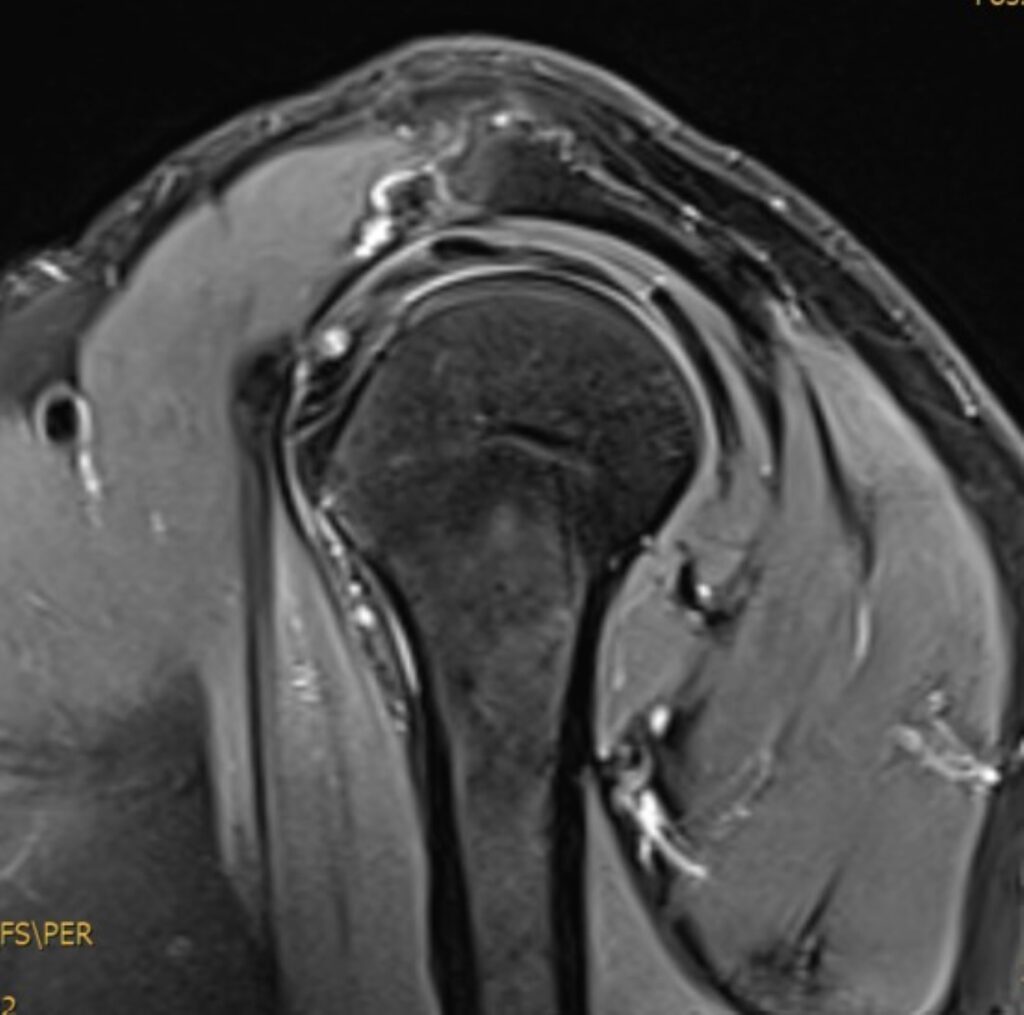

Die Magnetresonanztomographie der Schulter, kurz MRT Schulter genannt, ist eine bildgebende Untersuchung, die detaillierte MRT Bilder der Schulterstrukturen liefert, ohne Röntgenstrahlen zu verwenden. Sie ermöglicht die präzise Diagnose von Schulterschmerzen, Verletzungen, Arthrose und weiteren Erkrankungen der Schulter.

Eine Magnetresonanztomographie (MRT) oder auch Kernspintomographie der Schulter ist eine schmerzlose bildgebende Untersuchung, die ermöglicht die Strukturen im Schulterbereich präzise darzustellen. Es handelt sich hierbei um Querschnittbilder, die mithilfe von Magnetfeldern und Radiowellen ohne den Einsatz von ionisierender Strahlung erstellt werden. Mit der MRT können Knochen, Weichteile wie Muskeln und Sehnen, Gelenke sowie Nerven und Blutgefäße in der Schulterregion abgebildet werden. Dies ermöglicht die Diagnose von Schulterschmerzen, Verletzungen, Arthrose, Entzündungen und anderen Erkrankungen.

Was sieht man bei einer MRT Schulter?

| Gelenke und Knochen | Frakturen, Arthritis, weitere Gelenk-/Knochenprobleme |

| Bänder und Sehnen | Verletzungen oder Entzündungen |

| Schleimbeutel | Entzündung oder Schwellung |

| Rotatorenmanschette | Verletzungen oder Risse |

| Labrum | Verletzungen oder Risse |

| Nerven und Blutgefäße | Nervenkompression oder Gefäßveränderungen |